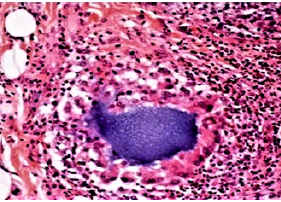

Figure 6a: Some clusters of granulocytes may suggest phagocytized bacteria but are no proof for their possible cause in granulomas [1].

The second “proof” was a slide with approximately 20 Grampositive cocci [17] scattered on a line in non-reactive tissue but not on the surface of the surrounding Aquamid droplets. If these bacteria would have multiplied in living tissue, at least some typical mononuclear cells would have shown up. On other parts of the slides, granulocytes were detected (Figure 6a & 6b). All initially accused bacterial strains are not found on human skin but must be air borne bacteria, most probably.